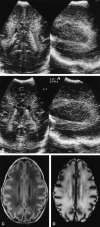

Background and purpose: In the early 1980s, diagnosing periventricular leukomalacia (PVL) in neonates by using cranial sonography was possible for the first time. Our purpose was to investigate the possibility of diagnosing PVL in the acute stage by using MR imaging. We evaluated early MR features of hypoxic-ischemic brain injury in neonates with periventricular densities (flares) on cranial sonograms to determine the added value of MR imaging over sonography alone for early diagnosis of brain damage.

Results: Fifty infants were classified according to the highest sonographic grade up to the day of MR imaging: 23 infants had sonographic grade 1 (flares < 1 week), 15 had sonographic grade 2 (flares > or = 1 week), four had sonographic grade 3 (small localized cysts), and eight had sonographic grade 4 (extensive periventricular cysts); none had sonographic grade 5 (multicystic leukomalacia) on the day of MR imaging. Overall, the additional information provided by MR imaging (over sonography alone) consisted of the depiction of hemorrhagic lesions in 64% of the infants. Extent and severity of the hemorrhages varied from isolated punctate lesions to extensive hemorrhages throughout the white matter; the latter were followed by cystic degeneration at autopsy in two infants. In nine of the 12 infants with cystic PVL, MR images showed more numerous or more extensive cysts. In addition, in two infants, MR images showed cysts not present on sonograms. In 32% of the infants, MR imaging provided no additional information; in these children, all but one had flares on sonograms whereas MR images showed no abnormalities or a zone of mild periventricular signal change.

Conclusion: MR imaging can depict the precise site and extent of hypoxic-ischemic brain injury at an earlier stage and allows a wider differentiation of lesions as compared with sonography alone. Hemorrhagic PVL is considered to be rare, but was present in 64% of our study population.